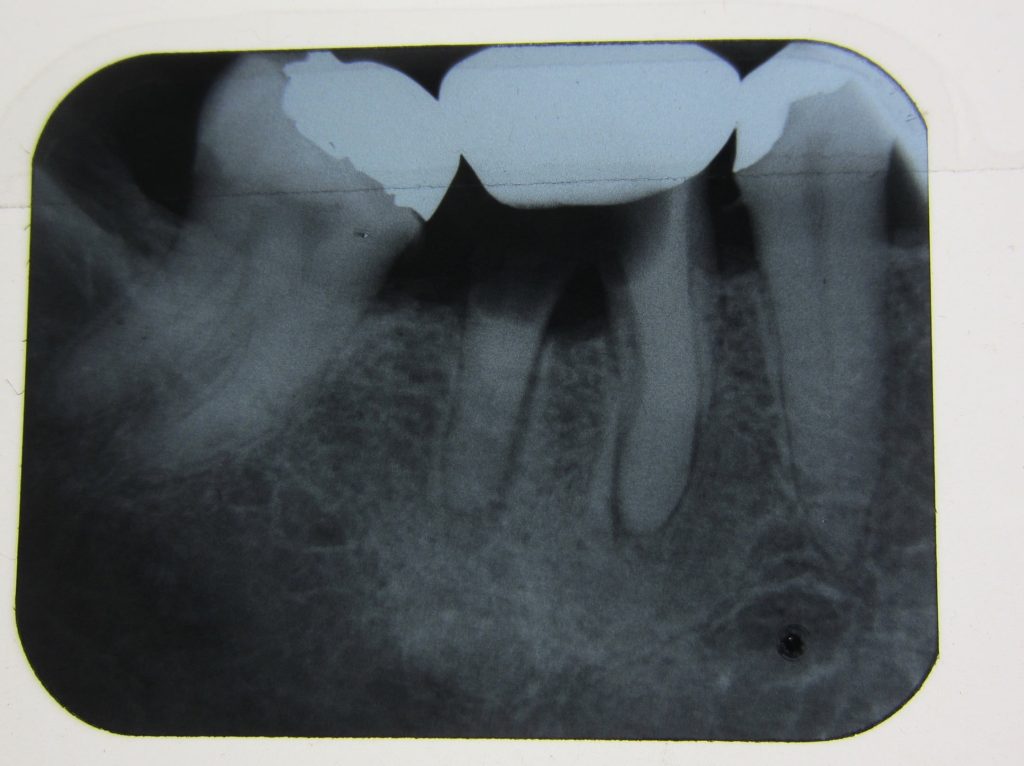

Firstly an x-ray could be done to see why the tooth is failing. Sometimes you can carry out root canal treatment and then crown the teeth. But there is no guarantee and the teeth could still fail underneath.

Many NHS dentists would even find the teeth above too difficult to fix, let alone remove.